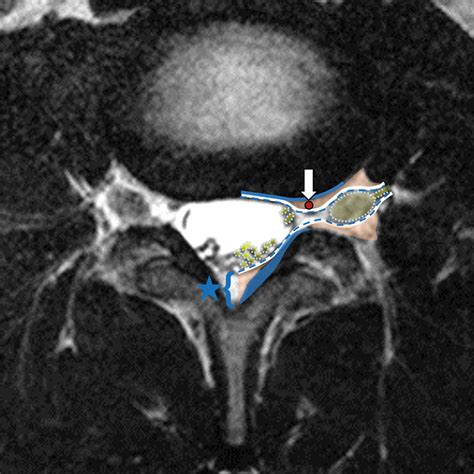

1 level - Cervical interlaminar epidural steroid injection, 3 Level Lu

1 level - Cervical interlaminar epidural steroid injection, 3 Level Lu ...